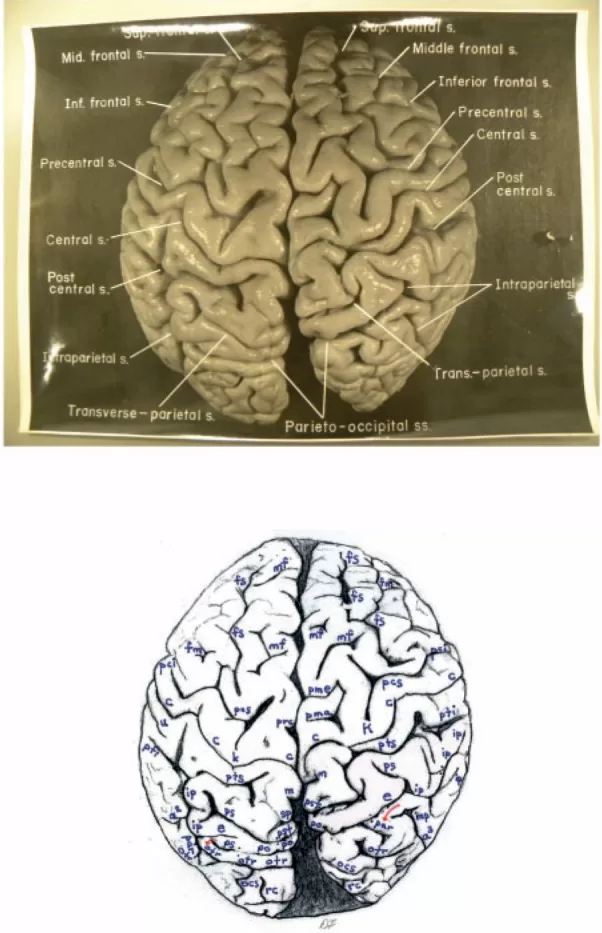

Top: Dorsal photograph of Einstein’s brain with original labels. Bottom: Our identifications. a2 = angular; a3 = anterior occipital; c = central; e = processus acuminis; fm = midfrontal; fs = superior frontal; inp = intermediate posterior parietal; ip = intraparietal; m = marginal; mf = medial frontal; ocs = superior occipital; otr = transverse occipital; par = paroccipital; pci = precentral inferior; pcs = precentral superior; pma = marginal precentral; pme = medial precentral; po = parieto-occipital; prc = paracentral; ps = superior parietal; pst = transverse parietal; pti = postcentral inferior; pts = postcentral superior; rc = retrocalcarine; u = unnamed. k = presumed motor cortex for right hand; K = ‘knob’ representing motor cortex for left hand. In both hemispheres, e limits anteriorly the first annectant gyrus, a pli de passage of Gratiolet that connects the parietal and occipital lobes, indicated by red arrows (see also Fig. 7). This figure is reproduced with permission from the National Museum of Health and Medicine.Top: Photographs of the left (L) and right (R) lateral surfaces of Einstein’s brain taken with the front of the brain rotated toward the viewer, with original labels. Bottom: Our identifications. Numbers 1–4 indicate four gyri in Einstein’s right frontal lobe, rather than three as is typical; K = ‘knob’ representing motor cortex for left hand. Submerged gyri are shaded red near the diagonal sulcus on each side. It is clear from the left hemisphere that the posterior ascending limb of the Sylvian fissure and the postcentral inferior sulcus are not confluent, contrary to the literature. Sulci: a = additional inferior frontal; a1 = ascending branch of the superior temporal sulcus; a2 = angular; aS = posterior ascending limb of the Sylvian; c = central; d = diagonal; dt = descending terminal branch of the Sylvian; fi = inferior frontal; fm = midfrontal; fs = superior frontal; ht = posterior terminal horizontal branch of the Sylvian; ip = intraparietal; mf = medial frontal; pci = precentral inferior; pcs = precentral superior; pma = marginal precentral; pti = postcentral inferior; pts = postcentral superior; R = ascending ramus of anterior Sylvian fissure; R’ = horizontal ramus of anterior Sylvian fissure; S = Sylvian fissure; sa = sulcus acousticus; sca = subcentral anterior; scp = subcentral posterior; sip = intermedius primus of Jensen; ti = inferior temporal; tri = triangular; ts = superior temporal; tt = transverse temporal; u = unnamed; W = fronto-marginal of Wernicke. 1 = superior frontal gyrus; 2 = atypical superior middle frontal gyrus; 3 = atypical inferior middle frontal gyrus; 4 = inferior frontal gyrus (usually the ‘inferior third frontal gyrus’). The figure reproduced with permission from the National Museum of Health and Medicine.Top: Photographs of the left (L) and right (R) lateral surfaces of Einstein’s brain taken from a traditional view, which lack original labels. Bottom: Our identifications. Numbers 1–4 on the right hemisphere indicate four gyri in Einstein’s right frontal lobe, rather than three as is typical. Sulci: a = additional inferior frontal; a1 = ascending branch of the superior temporal sulcus; a2 = angular; a3 = anterior occipital; aS = posterior ascending limb of the Sylvian; c = central; d = diagonal; dt = descending terminal branch of the Sylvian; e = processus acuminis; fi = inferior frontal; fm = midfrontal; fs = superior frontal; ht = posterior terminal horizontal branch of the Sylvian; inp = intermediate posterior parietal; ip = intraparietal; mf = medial frontal; ocl = lateral occipital; ocs = superior occipital; otr = transverse occipital; par = paroccipital; pci = precentral inferior; pcs = precentral superior; ps = superior parietal; pti = postcentral inferior; pts = postcentral superior; R = ascending ramus of anterior Sylvian fissure; R’ = horizontal ramus of anterior Sylvian fissure; S = Sylvian fissure; sa = sulcus acousticus; sca = subcentral anterior; scp = subcentral posterior; sip = intermedius primus of Jensen; ti = inferior temporal; tri = triangular; ts = superior temporal; tt = transverse temporal; u = unnamed. 1 = superior frontal gyrus; 2 = atypical superior middle frontal gyrus; 3 = atypical inferior middle frontal gyrus; 4 = inferior frontal gyrus (usually the ‘inferior third frontal gyrus’). K = ‘knob’ representing motor cortex for left hand. The figure is reproduced with permission from the National Museum of Health and Medicine.Top: Photographs of the left (L) and right (R) lateral surfaces of Einstein’s brain taken with the back of the brain rotated towards the viewer, with original labels. Bottom: Our identifications. The arrows indicate the pre-occipital notch at the inferolateral border of each hemisphere, which indicate the approximate inferior boundary between the lateral surfaces of the temporal and occipital lobes; on the right, an apparent artificial cut severed the rostral tip (shaded red) of a gyrus in the posterior part of the inferior temporal lobe. This cut appears to be a lateral extension of that observed on the right side of the base of the brain (Fig. 6). Typically, the supramarginal gyrus surrounds the posterior ascending limb of the Sylvian, and the angular gyrus surrounds the upturned end(s) of superior temporal sulcus. These gyri are separated approximately at the level of the intermedius primus sulcus of Jensen and together form the inferior parietal lobule. The supramarginal gyri are shaded blue; the angular gyri are aqua. In the left hemisphere, part of the cortical region above posterior terminal horizontal branch of the Sylvian is shaded an inbetween colour because it could arguably belong to either gyrus. Einstein’s inferior parietal lobules have different shapes in the two hemispheres, and appear to be relatively larger on the left side. Sulci: a1 = ascending branch of the superior temporal sulcus; a2 = angular; a3 = anterior occipital; aS = posterior ascending limb of the Sylvian; c = central; dt = descending terminal branch of the Sylvian; e = processus acuminis; ht = posterior terminal horizontal branch of the Sylvian; i = inferior polar; inp = intermediate posterior parietal; ip = intraparietal; lc = lateral calcarine; oci = inferior occipital; ocl = lateral occipital; ocs = superior occipital; otr = transverse occipital; par = paroccipital; ps = superior parietal; pti = postcentral inferior; pts = postcentral superior; rc = retrocalcarine; S = Sylvian fissure; scp = subcentral posterior; sip = intermedius primus of Jensen; ti = inferior temporal; ts = superior temporal; u = unnamed. The figure is reproduced with permission from the National Museum of Health and Medicine.Top: Photograph of a frontal view of Einstein’s brain in an unconventional orientation, with original labels. Bottom: Our identifications of sulci. a = additional inferior frontal; fi = inferior frontal; fm = midfrontal; fs = superior frontal; mf = medial frontal; S = Sylvian fissure; ts = superior temporal; W = fronto-marginal of Wernicke. The figure is reproduced with permission from the National Museum of Health and Medicine.Top: Separate photographs of the right (R) and left (L) basal views of Einstein’s bisected brain with cerebellum removed and original labels. Bottom: Our identifications. The two photographs are not to the same scale and the right hemisphere is rotated slightly laterally compared with the left, as suggested by a published basal photograph of the entire brain with its cerebellum attached (Witelson et al., 1999b). The base of Einstein’s brain appears to have been accidentally cut, perhaps with a scalpel, as indicated in red shading. This may have occurred during removal of the dura mater (tentorium cerebelli) that separates the dorsum of the cerebellum from the inferior surface of the occipital lobes. Magnifying the photographs on a computer screen should facilitate observation of these cuts. See Fig. 4 for an extension of this cut that reached the right lateral surface of the temporal lobe where it severed the tip of a gyrus (shaded in red). Sulci: arc = arcuate orbital; col = collateral; fi = inferior frontal; i = inferior polar; mo = medial orbital; oa = anterior orbital; oal = lateral anterior orbital; oci = inferior occipital; oct = occipito-temporal; op = posterior orbital; opl = lateral posterior orbital; os = olfactory; R’ = horizontal ramus of anterior Sylvian fissure; rh = rhinal; ti = inferior temporal. Abbreviations of other features: los = lateral olfactory stria; mb = mammillary body; mos = medial olfactory stria; ob = olfactory bulb; on = optic nerve; ot = olfactory tract. The figure is reproduced with permission from the National Museum of Health and Medicine.Top: Photograph of an occipital view of Einstein’s brain in an unconventional orientation, with original labels. Bottom: Our identifications. In both hemispheres, a processus acuminis limits anteriorly the first annectant gyrus, a pli de passage of Gratiolet that connects the parietal and occipital lobes, indicated by red arrows (see also Fig. 1). See Fig. 10B for shading of the superior and inferior parietal lobules and the occipital lobe on this image. Sulci: a2 = angular; a3 = anterior occipital; c = central; cu = cuneus; e = processus acuminis; inp = intermediate posterior parietal; ip = intraparietal; lc = lateral calcarine; m = marginal; oci = inferior occipital; ocl = lateral occipital; ocs = superior occipital; otr = transverse occipital; par = paroccipital; pcs = precentral superior; po = parieto-occipital; ps = superior parietal; pst = transverse parietal; pti = postcentral inferior; pts = postcentral superior; rc = retrocalcarine; sp = subparietal; ss = superior sagittal; ti = inferior temporal; ts = superior temporal. The figure is reproduced with permission from the National Museum of Health and Medicine.Top: Photographs of the left (L) and right (R) medial surfaces of Einstein’s brain with original labels. Bottom: Our identifications. Arrows indicate sulci that extend onto the dorsolateral surface of the brain. Sulci: ac = anterior calcarine; apo = anterior parolfactory; c = central; ca = callosal; cal = calcarine; ci = cingulate; cu = cuneus; li = lingual; lp = limiting sulcus of precuneus; m = marginal; mf = medial frontal; otr = transverse occipital; pc = paracalcarine; pma = marginal precentral; pme = medial precentral; po = parieto-occipital; prc = paracentral; pst = transverse parietal; rc = retrocalcarine; ri = inferior rostral; rs = superior rostral; si = inferior sagittal; sp = subparietal; ss = superior sagittal; u = unnamed. Other abbreviations: cc = corpus callosum; f = fornix; hpt = hypothalamus; ipo = parieto-occipital incisure; sep = septum pellucidum; th = thalamus. See text for discussion. The figure is reproduced with permission from the National Museum of Health and Medicine.Top: Photograph of Einstein’s right insula after removal of the opercula, with original labels. Bottom: Our identifications of sulci: aps = anterior periinsular; cis = central insular; pcis = precentral insular; pis = postcentral insular; sis = short insular; sps = superior periinsular; Other identification: ia = apex of insula. The figure is reproduced with permission from the National Museum of Health and Medicine.